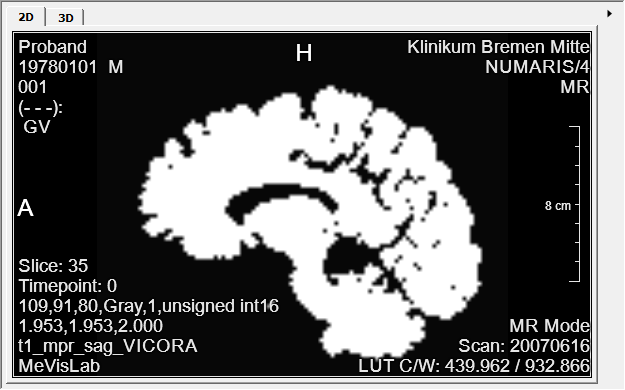

In this example, you will segment the brain of an image and show the segmentation results as an overlay on the original image.

Add a LocalImage module to your workspace and select load $(DemoDataPath)/BrainMultiModal/ProbandT1.dcm. Add a View2D module and connect both as seen below.

You can now also add a View3D to show your segmentation in 3D. Your final result should look similar to this.